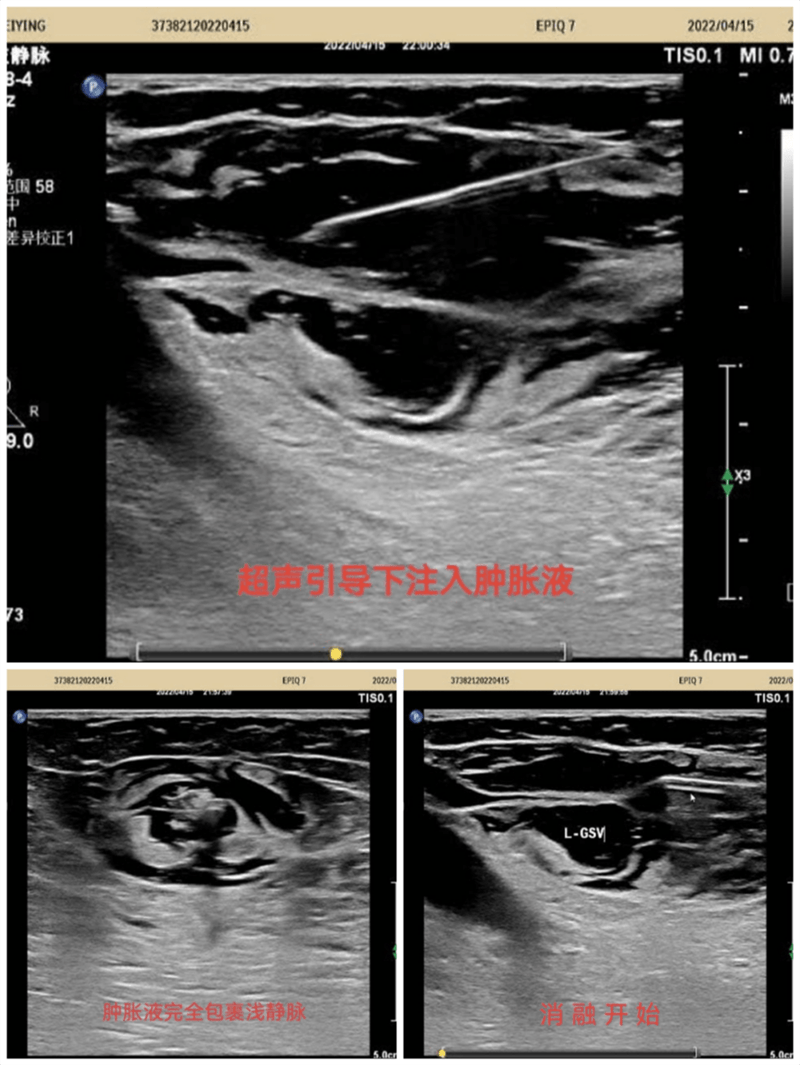

超声引导下标记大隐静脉及曲张静脉部位走行,体表投影部位标记,在彩色多普勒超声静脉模式引导下实时监测,确定穿刺点,局麻下穿刺进针,确定穿刺成功后置入导丝,拔除穿刺针并沿导丝置入7F鞘管,拔出导丝,沿鞘管将消融电极置入要消融的大隐静脉主干内,注入肿胀麻醉液,确认大隐脉闭合,开启移动射频消融导管,消融完毕后拔除鞘管及射频导管再次超声探查隐股静脉交界处,确定无血栓形成。